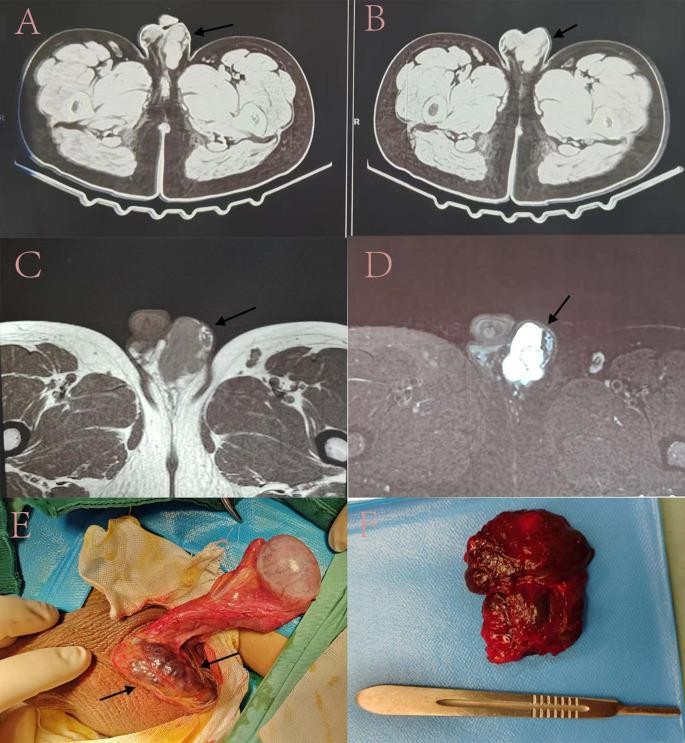

We presented a case report involving a sixteen-year-old male, detailing symptoms, physical examination, imaging studies, diagnosis, and treatment. We conducted a thorough literature analysis of case reports and examined their clinical characteristics, pathological categorization, recurrence, and complications.

Our study comprised 21 patients with scrotal hemangioma. The average age was 27.14 years, with a range from 21 days to 84 years. 57.1% of the hemangiomas affected the organs. 61.9% of patients were situated on the right side of the scrotum. Ninety percent of patients experienced no pain. Merely 33.3% of patients exhibited additional symptoms, which encompassed azoospermia, hemorrhage, calcification, hydrocele, thrombosis, and ulceration. The predominant pathological classification was cavernous scrotal hemangioma, representing 38.1% of the cases. All patients received surgical resection, and the majority experienced neither relapse nor postoperative complications.